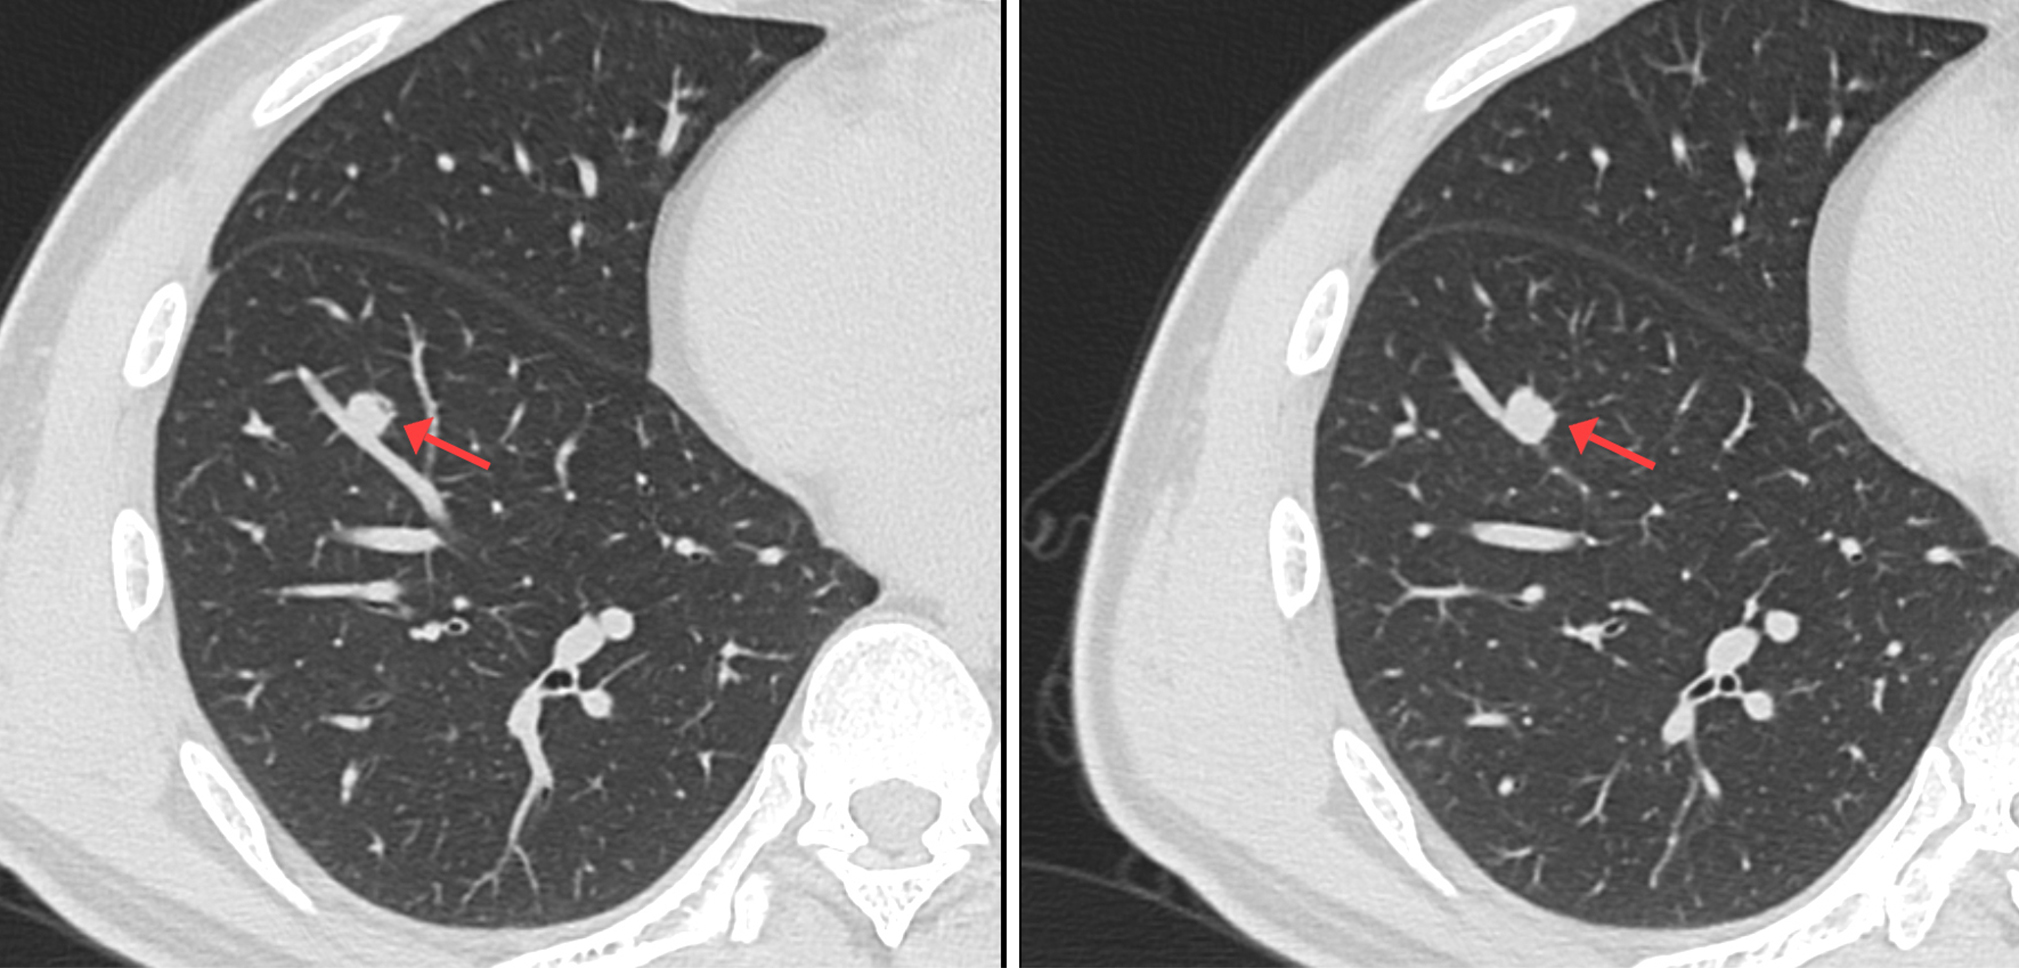

CT影像圖

CT示:右肺上葉尖段磨玻璃結(jié)節(jié),考慮腫瘤性病變可能,建議PET/CT檢查。